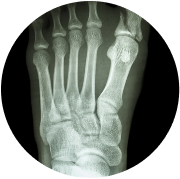

- Digital X-rays

- Diagnostic Evaluations